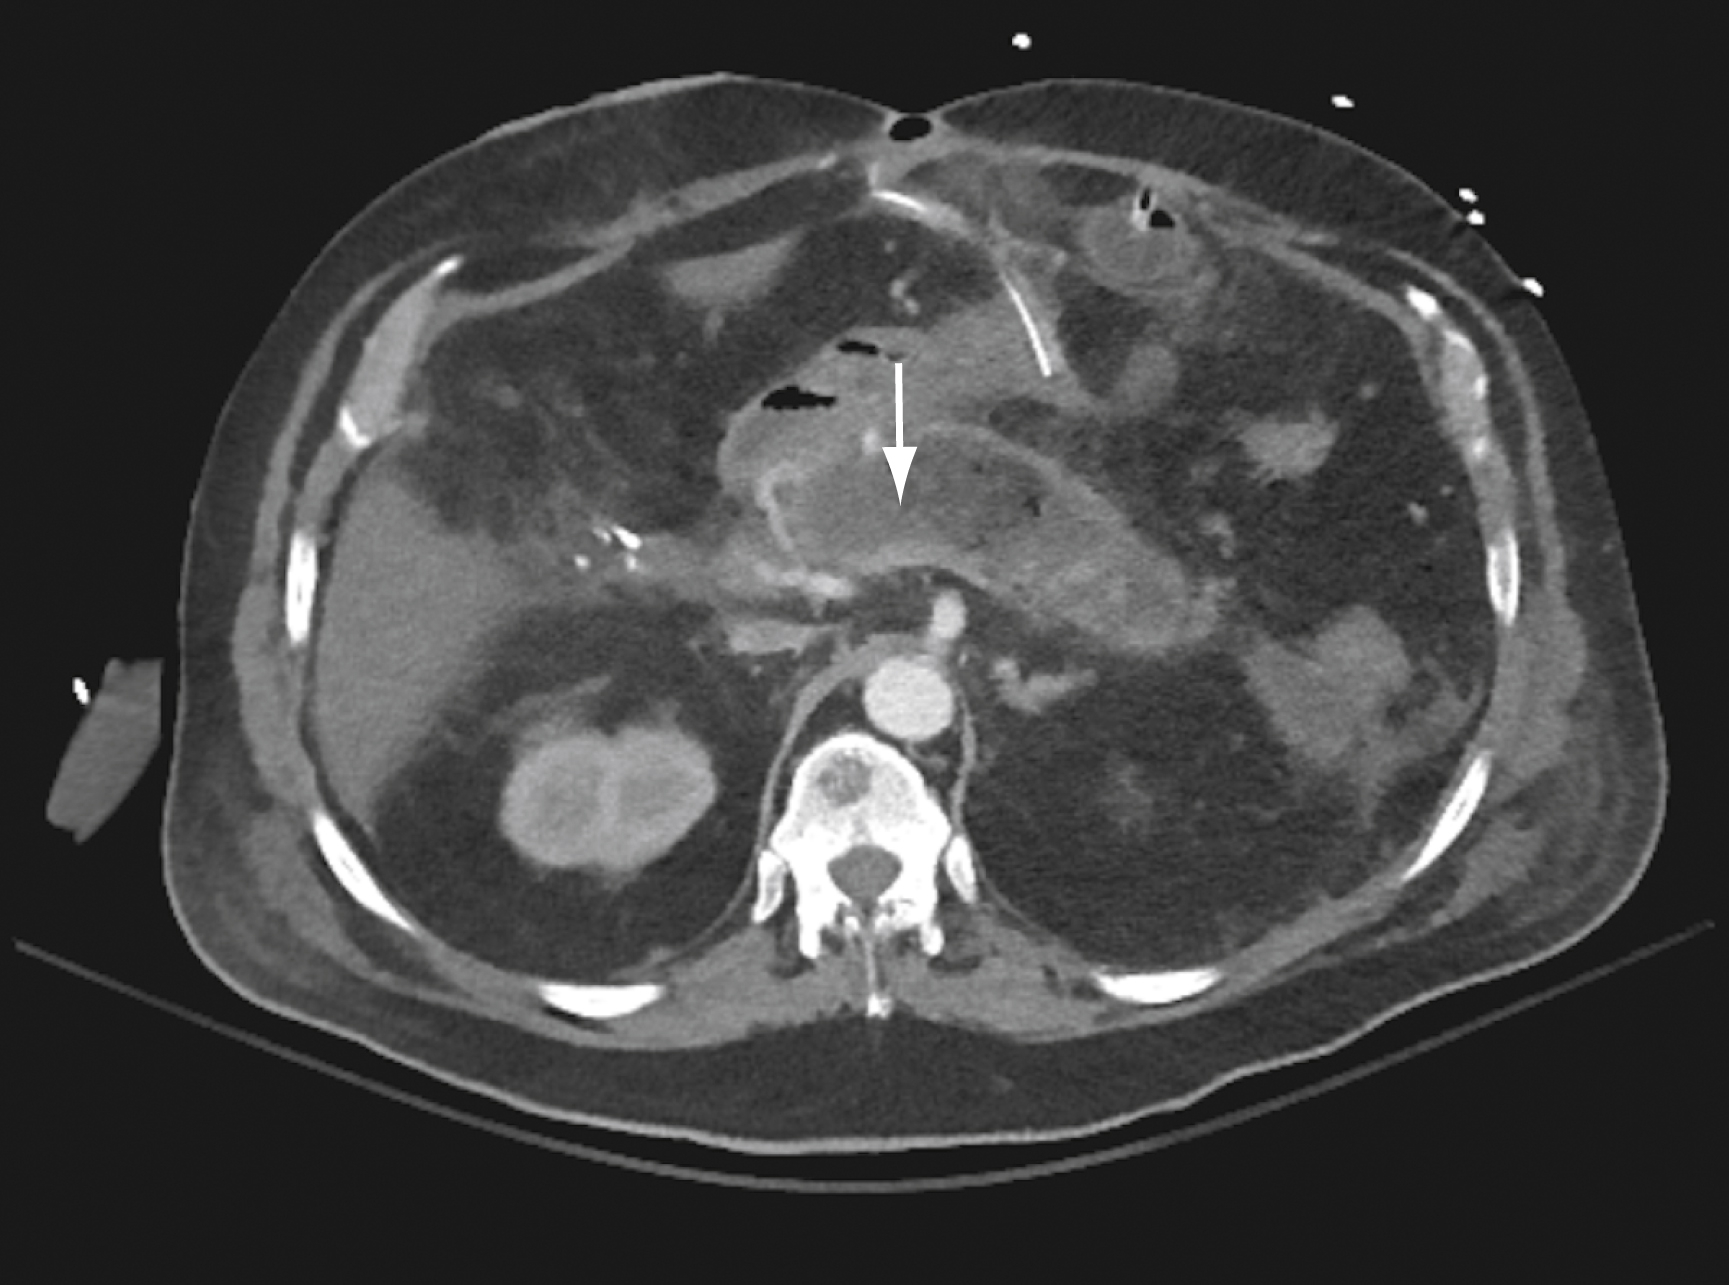

If CT is performed, it should be done with intravenous (IV) contrast. The CT scan is normal in 15% to 30% of patients with mild cases of pancreatitis. Contrast-enhanced CT has a greater than 90% sensitivity and specificity in the diagnosis of acute pancreatitis. Abnormal findings include pancreatic parenchymal enlargement with lack of enhancement, loss of its typical texture and borders, and surrounding retroperitoneal fat stranding ( Fig. 77.2 ). Pancreatic necrosis is suggested by areas demonstrating no enhancement ( Fig. 77.3 ). In cases for which contrast is contraindicated, CT without contrast may still be useful; alternatively, MRI can be performed.

Computed tomography Scan Showing Necrotizing Pancreatitis.

There is decreased enhancement of the pancreas where the parenchyma has been replaced by necrotic fluid (arrow) .

Courtesy Dr. Cash Horn.